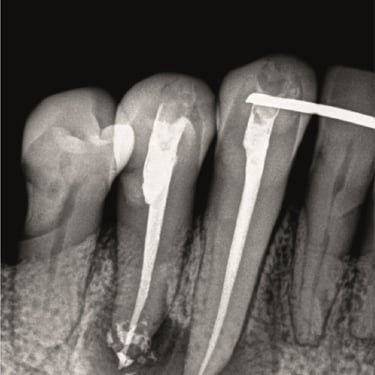

Retratamento de canal:

Correção de tratamentos mal sucedidos ou que voltaram a apresentar sintomas.

CASOS CLÍNICOS ENDO

Abaixo você encontra fotos de alguns dos tratamentos realizados.